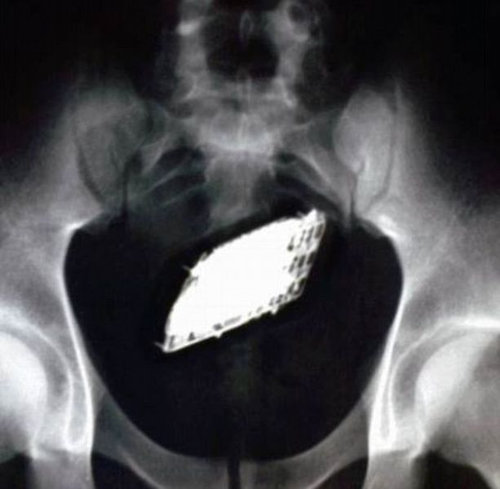

胃袋の中。